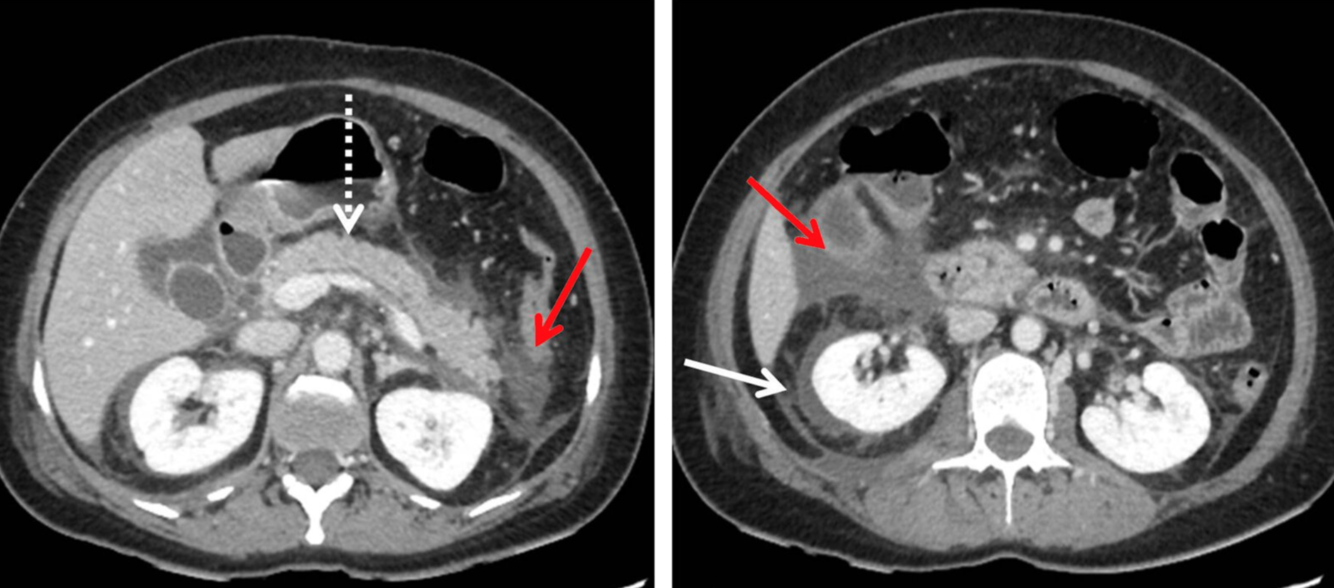

TDM de l’abdomen (avec produit de contraste ; plan axial)

Une collection liquide péripancréatique aiguë homogène non encapsulée (APFC) sans composants solides est visible. L’aspect est caractéristique de la pancréatite interstitielle aiguë (non compliquée). Un échouage liquidien et graisseux peut être observé en avant du pancréas ainsi que dans les espaces pararénaux (flèches rouges). Il existe également du liquide périrénal (flèche blanche). Le tissu pancréatique (flèche en pointillés ; P) est rehaussé de manière homogène, sans signe de nécrose tissulaire.

Les APFC peuvent être uniques ou multiples et se développent généralement au début de la pancréatite aiguë. La persistance pendant plus de 4 semaines augmente la probabilité de développement d’un pseudokyste.